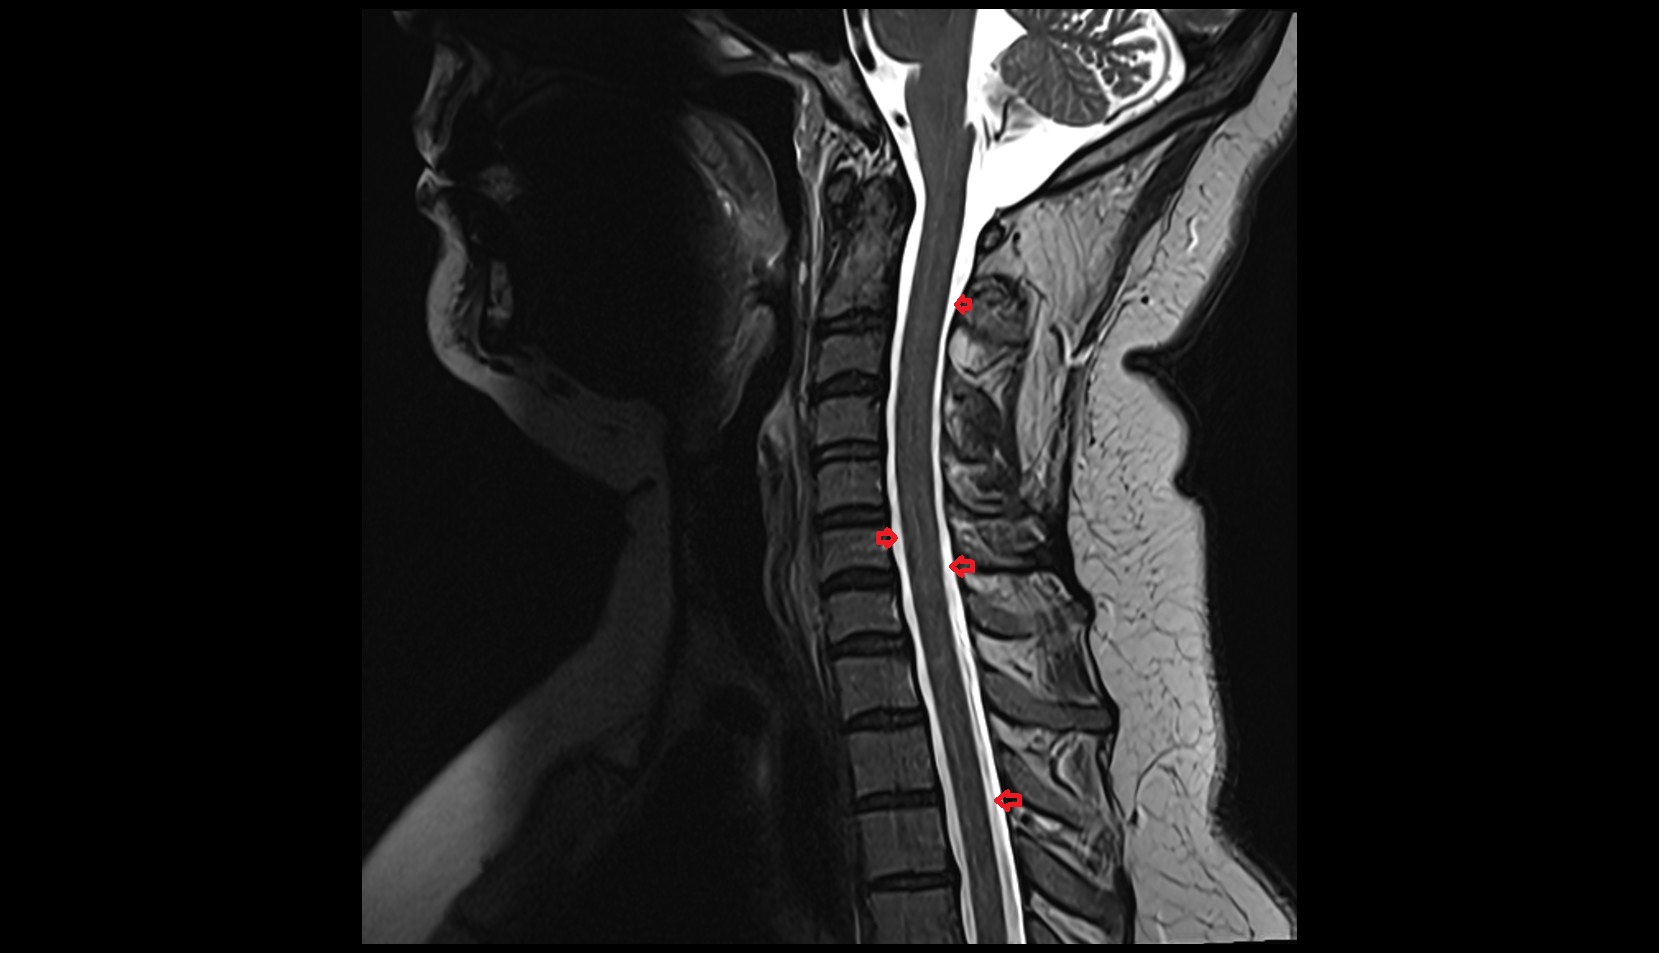

- Cervical spinal nerve 1 (C1)

- Cervical spinal nerve 2 (C2)

- Cervical spinal nerve 3 (C3)

- Cervical spinal nerve 4 (C4)

- Cervical spinal nerve 5 (C5)

- Cervical spinal nerve 6 (C6)

- Cervical spinal nerve 7 (C7)

- Cervical spinal nerve 8 (C8)

- Axis (C2 vertebra)

- C3–C4 intervertebral disc